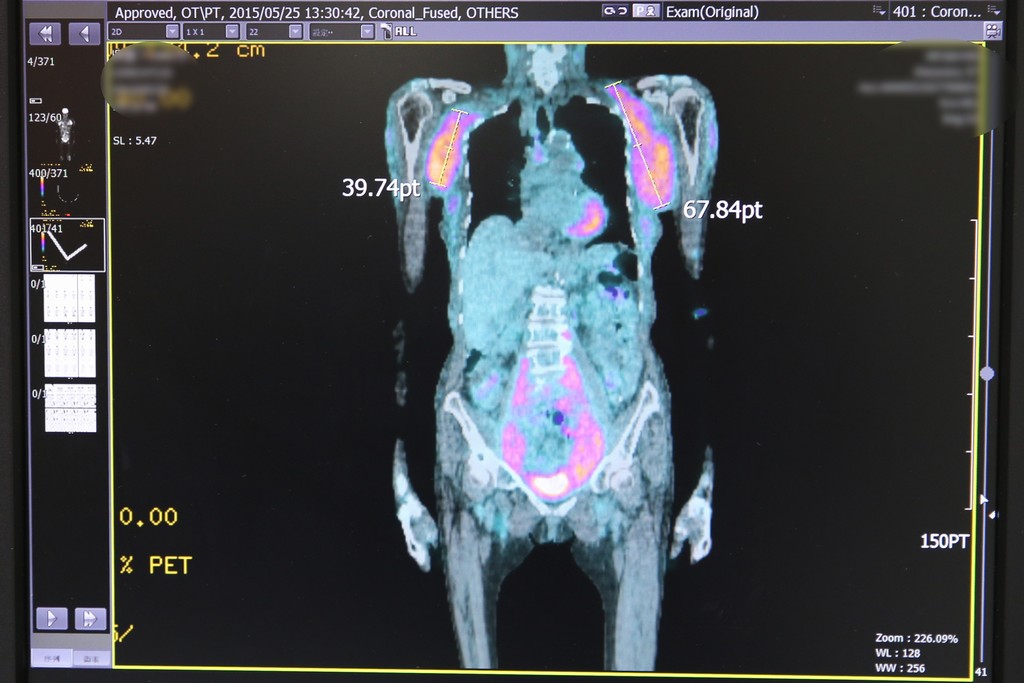

吳姓婦人是在七年前發現腋下腫大,原先不以為意,但腫瘤開始逐漸變大,就醫檢查發現是罹患罕見惡性淋巴癌「被套性細胞淋巴瘤」,經過化療搭配標靶藥物治療一年半後,又再度復發。

王佐輔主任指出,高惡性度被套性細胞淋巴瘤(Mantle Cell Lymphoma,MCL),好發在五十至七十歲長者,其中男性又比女性多三倍,因為初期症狀不明顯,七成病患在確診時已經較為後期,並出現淋巴結腫,常見侵犯部位為血液、骨髓、胃腸道、脾臟等等,是一種長期、復發率高的淋巴癌。

2017年十一月,衛福部健保署將治療被套性細胞淋巴瘤的新型口服標靶藥物納入健保給付作為二線治療,黃威翰表示,新型口服標靶藥物可抑制惡性B細胞生長及生存,使腫瘤縮小甚至消失,且副作用小,只有一成的病人使用後有輕微腹瀉及心律不整,只須注意藥物交互作用並嚴密監控心律不整。

這位罹患被套性細胞淋巴瘤再度復發的吳姓婦人,使用一年多的新型標靶藥物治療後,又能再繼續她最愛的運動,孫女黃小姐開心地說,還好新型標靶藥物有納入健保給付,不只減輕家裡的經濟負擔,也讓阿嬤不再害怕接受治療,現在她就像生病前一樣精神奕奕。